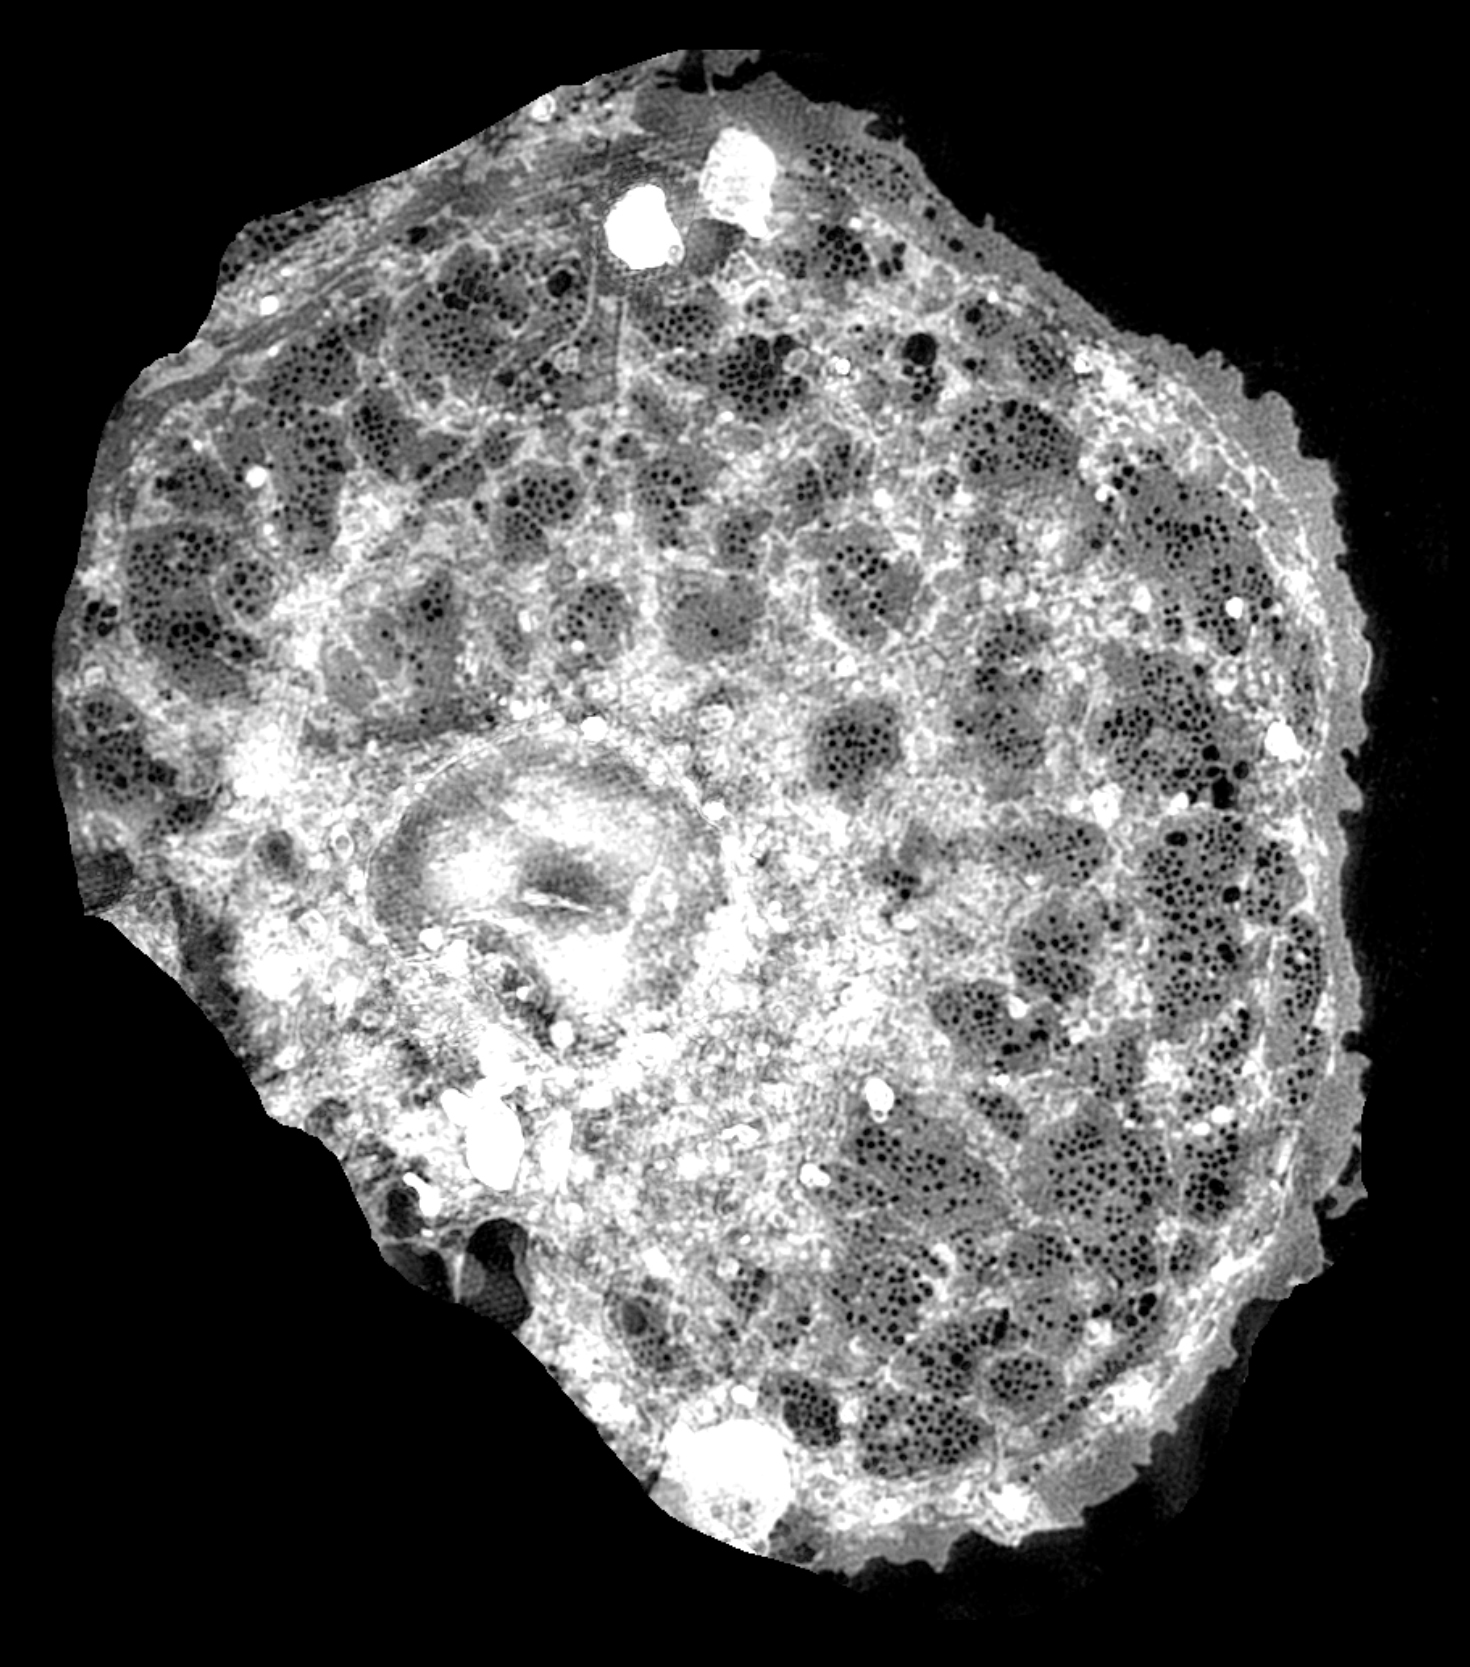

gesundes Altern unter dem Mikroskop: Sie entwickeln neuartige optische

Verfahren, mit denen sich die Leber mikroskopisch-hochauflösend

Husers

Arbeitsgruppe „Biomolekulare Photonik“ entwickelt höchstauflösende

Mikroskope, mit denen es möglich ist, Strukturen in Körperzellen

sichtbar zu machen und zu untersuchen, die herkömmliche optische

Mikroskope nicht darstellen können.